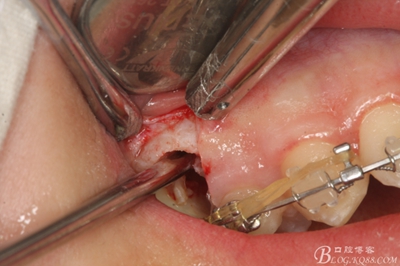

圖18.取出近中部分后,接著挺松15牙根的遠(yuǎn)中部分

圖19.挺松后,15的遠(yuǎn)中部分仍從合面狹小間隙通過取出。

圖20.取出的15遠(yuǎn)中部分

圖21.相鄰牙齒毫發(fā)無損,牙槽窩形態(tài)正常,無破壞。